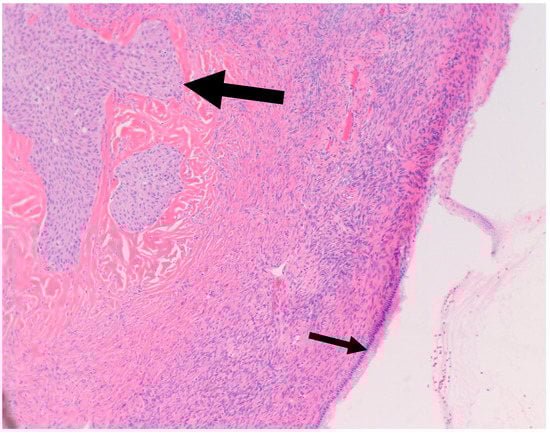

- Walthard cell rests: The differential diagnosis of benign BTs includes Walthard cell rests. Benign BTs contain a fibromatous background which is absent in Walthard cell rests.